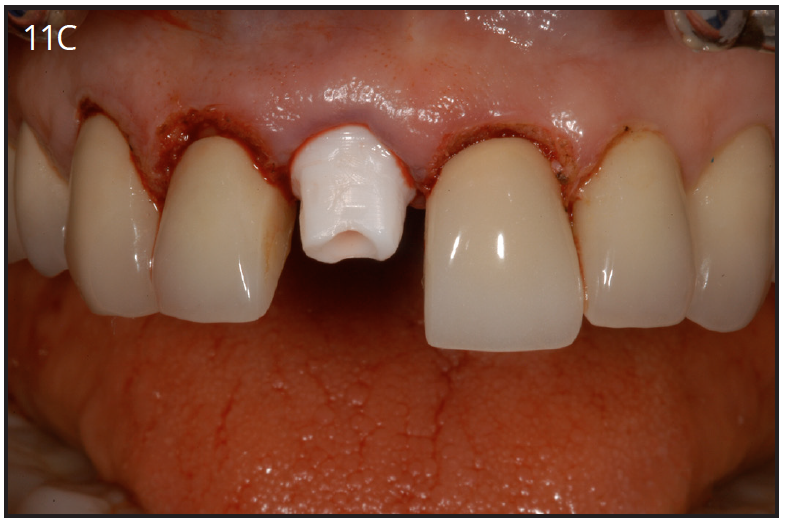

An implant most closely replicates the feel of a natural tooth. Once it is osseointegrated, many patients cannot differentiate an implant from a natural tooth. Furthermore, dental implants do not decay or need a root canal. Even though the cost is slightly more than a bridge, it is a great investment for the future, as implants usually last longer than a bridge. A 10-year report on posterior single implants shows a success rate of 97%.29 Once an implant is placed, an integration/healing time of approximately 4 months is necessary before final crown is placed. A temporary crown can be placed the same day the implant is placed. (Figures 11A-E)

Figure 11C – A zircon (white) abutment was attached immediately following the extraction and implant placement

Figure 11C

Figure 11D – Immediate placement of temporary crown over the abutment; laser crown lengthening was performed on the adjacent teeth to improve gingival symmetry

Figure 11D